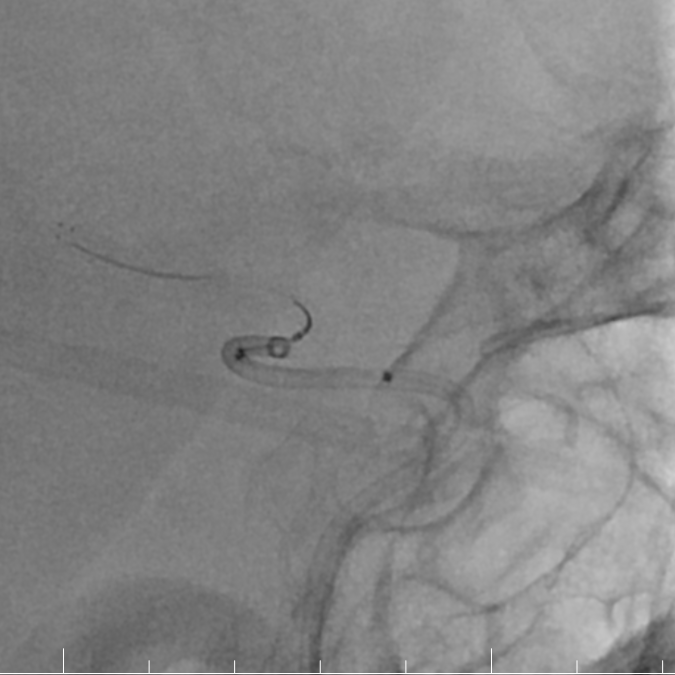

造影提示右侧大脑中动脉M2段下干闭塞。

动脉长鞘怎么置入有励可说|Locaste 088励楷长鞘及Tarvos微导丝在右侧大脑中动脉M2段取栓术中的应用_https://www.jmylbn.com_新闻资讯_第10张

动脉长鞘怎么置入有励可说|Locaste 088励楷长鞘及Tarvos微导丝在右侧大脑中动脉M2段取栓术中的应用_https://www.jmylbn.com_新闻资讯_第11张

Tarvos微导丝轻松超选,到达M1段。

动脉长鞘怎么置入有励可说|Locaste 088励楷长鞘及Tarvos微导丝在右侧大脑中动脉M2段取栓术中的应用_https://www.jmylbn.com_新闻资讯_第12张